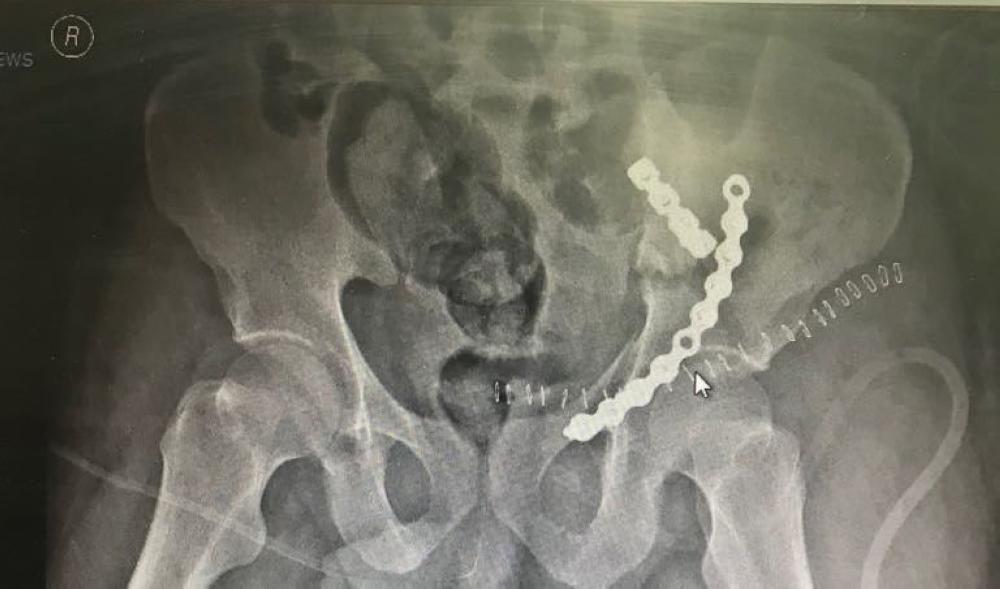

وتم استقبال المصاب وإجراء الإسعافات الأولية فور وصوله، ومتابعة التطورات إلى أن أستقرت حالته، وتم تثبيت الكسور بشريحتين إعادة بناء، بعد تحضير كل ما يلزم لإجراء التدخل الجراحي لتثبيت الكسور، والتعامل بمهارة خاصة مع التهتك الشديد بأنسجة الحوض وعضلات البطن، وتهتم أوردة الحوض.

وتحسنت حالة المريض بشكل ملحوظ كما أكدت الأشعة السينية بعد العملية نجاح هذا الإجراء الجراحي.